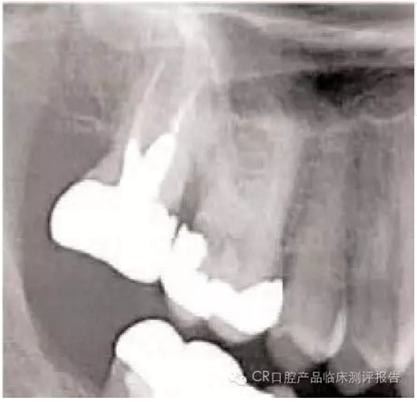

● 影像學(xué)檢查的要點(diǎn)

- 包括根尖:注意根尖的形狀(喇叭口、彎曲、融合、球形),有些情況需要牙根縱切。

- 找出牙根附近重要組織的影像:牙周膜(PDL)的缺口、上頜竇、血管神經(jīng)、高密度骨質(zhì)區(qū)域。根內(nèi)是否含有根管?(觀察比較難因?yàn)楦芤姿榛蚺c骨長(zhǎng)合)